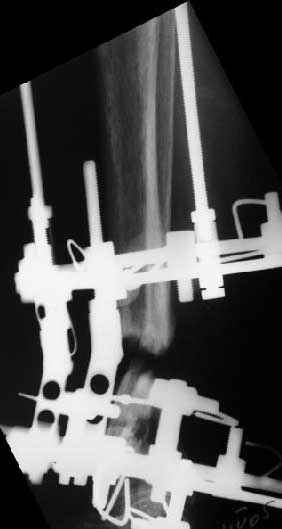

В общем, начали c аппарата - нложили, малоберцовую внизу пересекли, выбрали люфт, раз дальше сопротивление пошло - выведем постепенно.

Картинки приложены. Жду комментариев.

Аппарат - чтобы плавно исправить ось. В приложении - снимки на момент окончания коррекции в аппарате, фото с операции, и послеоперационная рентгенограмма.

Диаметр гвоздика 10,5 мм. Пришлось укорачивать до 23 см - уж очень миниатюрная дама, отверстия насверлил под 45 градусов, под 5 мм винты. По оси удалось сблизить до этого положения. Заперли гвоздь пока статически с планом через 2 месяца верхний винт убрать. Но это ей придется уже в Ташкенте сделать. Что скажете? Спасибо.

In attachment - x-rays at the end of alignment, the surgery, and result. The nail was cut to 23 cm. Four 45 degree holes were pre-drilled at the distal nail tip. The nail was locked statically

after some impaction. Dynamization is considered in 8 weeks. Any comments/critics?